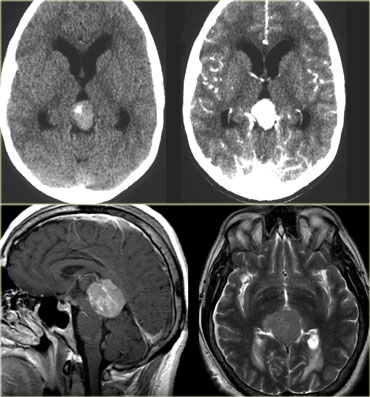

Ring enhancement

Ring enhancement is seen in metastases and high-grade gliomas.

It is also seen in non-tumorous lesions like abscesses, some MS-plaques and sometimes in an old hematomas.

On the left three different ring enhancing lesions.